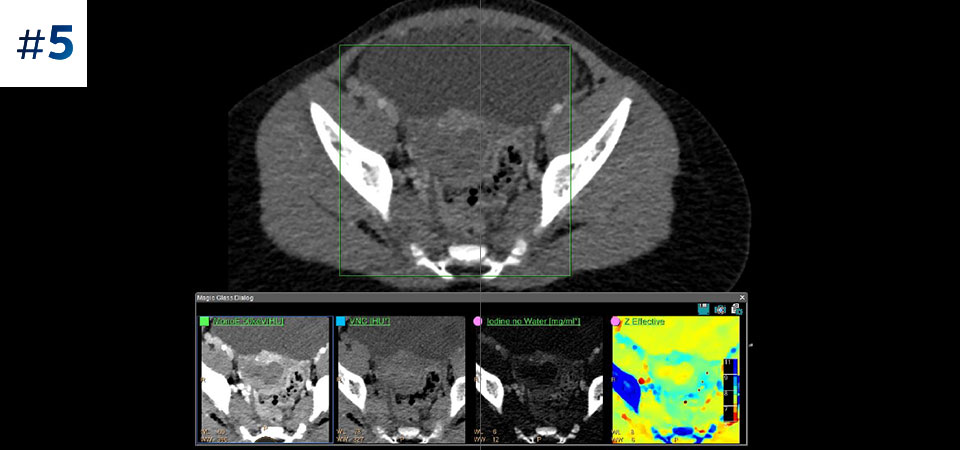

With detector-based spectral, you acquire multiple layers of data—conventional and spectral—within a single exposure and without special scan modes for improved tissue characterization and visualization.

Scan as usual A single scan for fast, low-dose conventional and spectral data for every patient, every time.

Reduced follow-up exams Improved tissue characterization and visualization may reduce the need for follow-up scanning for sub-optimal exams and incidental findings.

Across patient types Benefits a wide range of patient types from pediatric to bariatric.